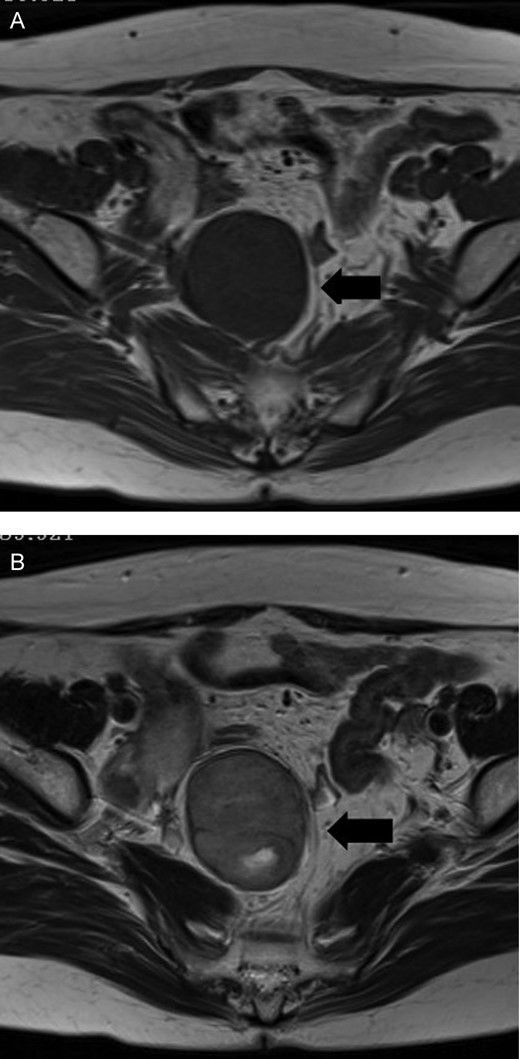

A 54-year-old woman was referred to our hospital with a mass in the pelvic cavity detected on chest-abdominal, CT done for investigation of breast cancer. She had no particular past and family history, and the physical examination was unremarkable. Ultrasonography of the pelvis revealed a 5 × 4.3 cm, solid mass separated from her right adnexa (Fig. 1). Contrast enhanced-CT showed a 5 × 4 cm, solid, well-defined, heterogeneous mass in the right side of the pelvic cavity (Fig. 2). MRI showed that the tumor demonstrated homogeneous hypointensity on T1-weighted images and heterogeneous slight hyperintensity on T2-weighted images (Fig. 3a and b). Sagittal sections of MRI demonstrated that the mass was intricately related to the anterior presacral fascia (Fig. 4). The preoperative diagnosis was a mesenteric gastrointestinal stromal tumor.

MRI shows that the tumor is a homogeneous hypointensity on T1-weighted images (A) and a heterogeneous slight hyperintensity on T2-weighted images (B) in a right side of the pelvic cavity.